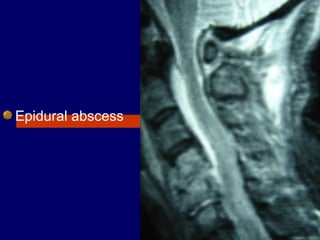

Epidural abscess

Epidural abscessEpidural abscess

Of the spinal column is

a rare but potentially

devastating disease.